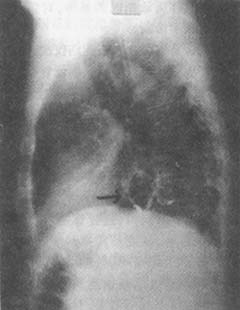

图2 食管裂孔疝X线

钡剂造影:膈上见胃囊